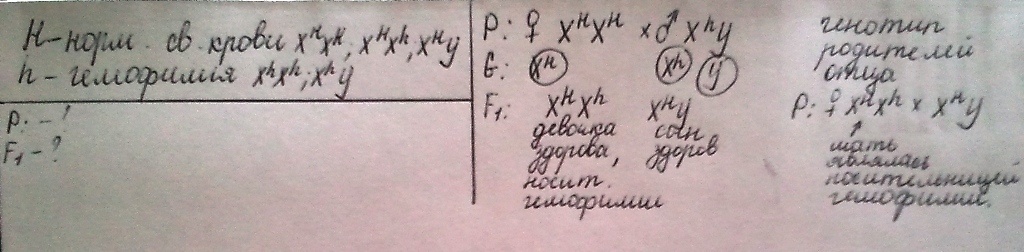

Генетика гемофилии: рецессивные гены и их проявления